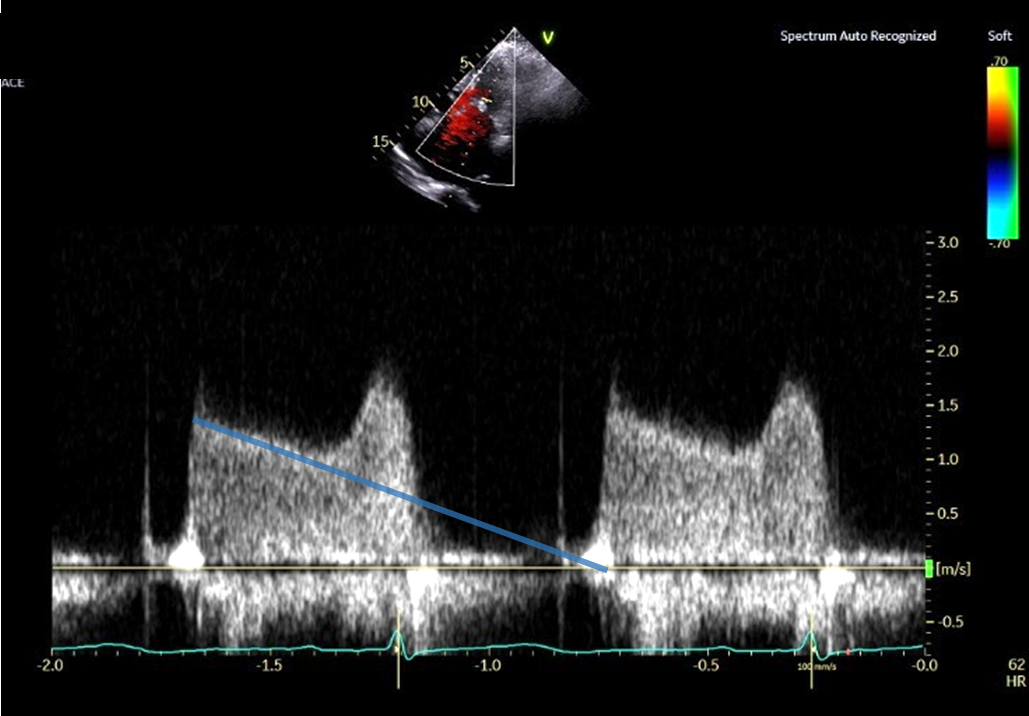

PHT法 拡張早期の急峻な部分から計測した場合 (No15_1)

PHT法 拡張早期の急峻な部分を避けて計測した場合 (No15_2)

① プラニメトリ法で僧帽弁口面積を計測する時相は収縮中期である

② 動画中の傍胸骨短軸断面において、僧帽弁交連部の癒合を認める

③ PHT法で弁口面積を求める際は、拡張早期の急峻な部分を避けて計測する

④ PHT法は僧帽弁狭窄をきたしていれば、リウマチ性、退行性のどちらでも使用することができる

⑤ 僧帽弁口面積を推定する方法である連続の式は、有意な大動脈弁逆流や僧帽弁逆流があっても使用することができる